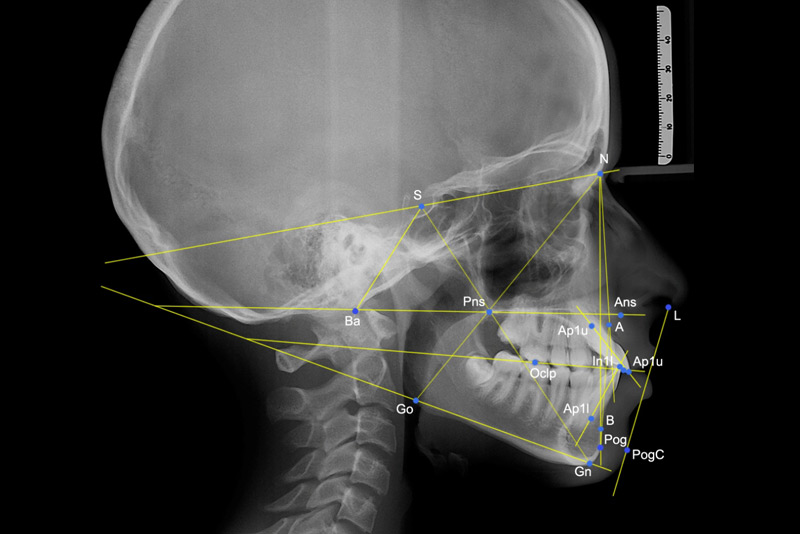

Obtiene una imagen lateral del cráneo del paciente; esto permite al técnico y dentista identificar el crecimiento y posición de la mandíbula y examinar patrones de crecimiento.

Esto permite al técnico y dentista identificar el crecimiento y posición de la mandíbula y examinar patrones de crecimiento.

Ejemplo de Imagen informativa